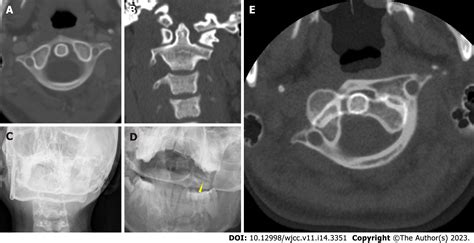

Diagnosing subluxation in pediatric patients involves a combination of clinical examination and imaging studies. The diagnostic process typically includes:

• Imaging Studies: X-rays, MRI, or CT scans may be used to visualize the joint and confirm the diagnosis. These imaging studies can help determine the extent of the subluxation and any associated injuries.